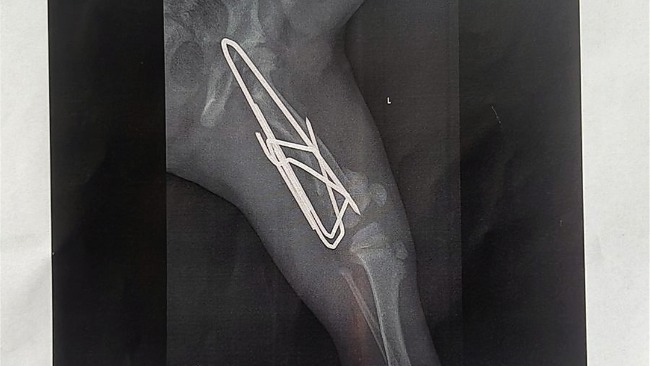

Kupili mnie ludzie, którzy chcieli bardzo mieć takiego przystojniaka jak ja, ale miałem wypadek, bawiąc się spadłem z tarasu na 2 piętrze, złamałem sobie nóżkę, moi właściciele zabrali mnie do kliniki, mam teraz taką metalową nóżkę i nie mogę się już bawić jak kiedyś. 😔 Ale najgorsze jest to że moi właściciele już mnie nie chcą 😥.

Pani z hotelu powiedziała mi, że jestem najsłodszym szczeniakiem jakiego widziała, i choć kuleję na jedną nóżkę, a z niej wystają jakieś metalowe druty, pokochała mnie i mówi że nie pozwoli bym trafił do jakiegoś "schroniska" - nie wiem, co to jest, ale to chyba nic dobrego. I tutaj potrzebne jest wsparcie, muszę nadal jeździć do kliniki, by wyleczyli moją nóżkę a to kosztuje trochę pieniędzy, a mojej nowej Pani na to nie stać, dlatego organizujemy zbiórkę, bym znów mógł się bawić jak kiedyś :)